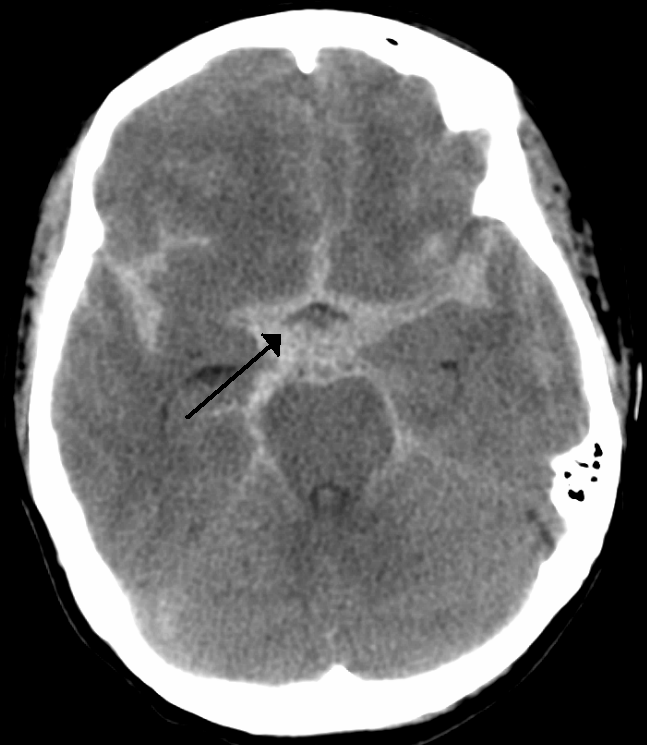

Subarachnoid Hemorrhage

Subarachnoid hemorrhage is hemorrhage that involves the subarachnoid area of the brain.

Subarachnoid hemorrhage symptoms include:

- Sudden “thunder clap” headache

- Worst headache of life

- Suddenly neck stiffness

A spinal tap in a patient with subarachnoid hemorrhage reveals xanthochromia (yellow hue due to bilirubin breakdown).